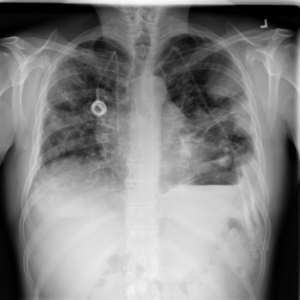

Figure 2: Examples of normal vs. abnormal images of considered datasets. Natural images: (first row) cars vs other classes of CIFAR10 dataset [1], (second row) digits “0” vs digits “1” – “9” of SVHN dataset [2]. Medical images: (third row) healthy tissue vs. tissue with metastases in H&E-stained lymph nodes images from Camelyon16 challenge [3], (fourth row) normal chest X-rays vs. chest X-rays with abnormal findings from NIH dataset [4].

Figure 6: Examples of normal (left) and anomaly (right) images of H&E-stained lymph node of Camelyon16 challenge [3] (top) and chest X-rays of NIH dataset [4] (bottom). We also showed the predicted anomaly score by the proposed method. The higher the score, the more likely to be an anomaly. Notice how the proposed method spots even the borderline cases.